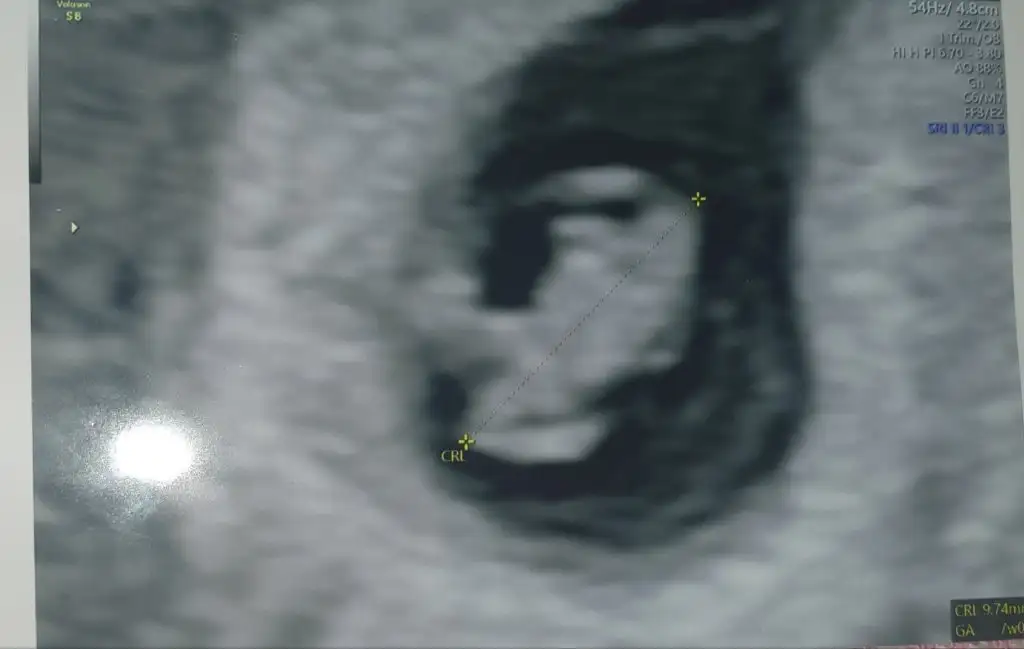

Benimkine de tahminde bulunur musunMerhaba millet

Ramzi teorisine göre cinsiyet tahmini yapacagim ilk ultrasyon resminizi atin bakiyim. Eger cinsiyetiniz belliyse hic söylemeeyin bakalm dogru tahmin edebilecekmiyim daha dogrusu ramzi teorisi hakli cikacak mi?

Benim görüntüleme bakarmisiniz 6 haftalik karından ultrasonKiz diyorum